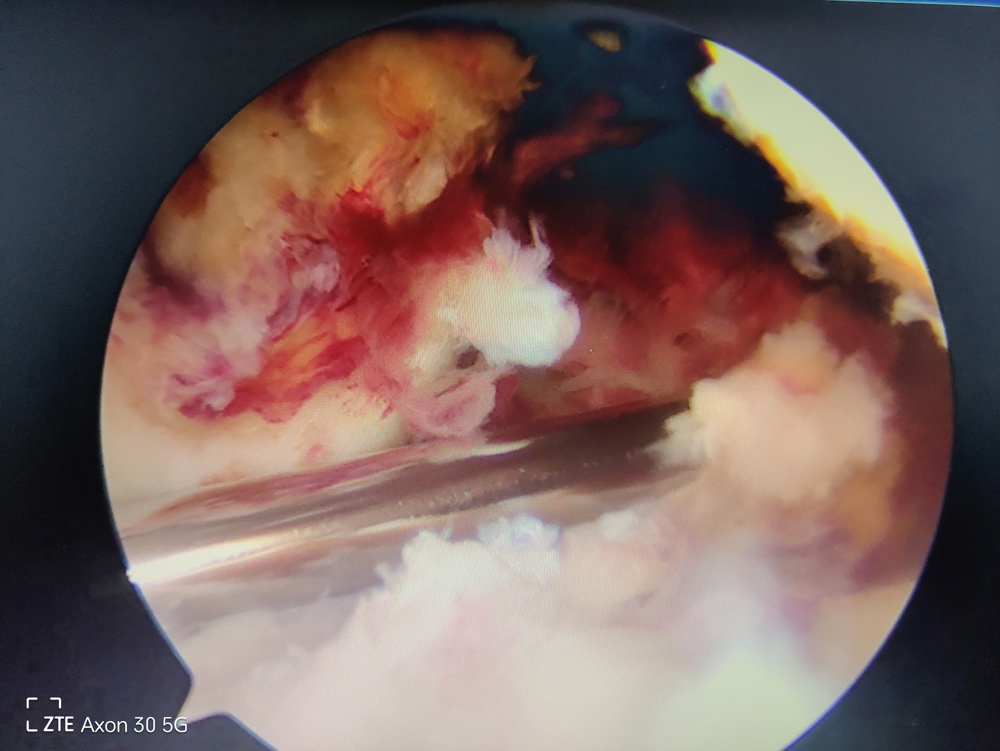

进入手术室麻醉(无疼痛)下检查见膝关节前后、侧方稳定性均极差。关节镜下见交叉韧带、内侧副韧带、内侧髌骨韧带、股四头肌腱、外侧半月板损伤。

关节镜下多发韧带断裂仅剩残端